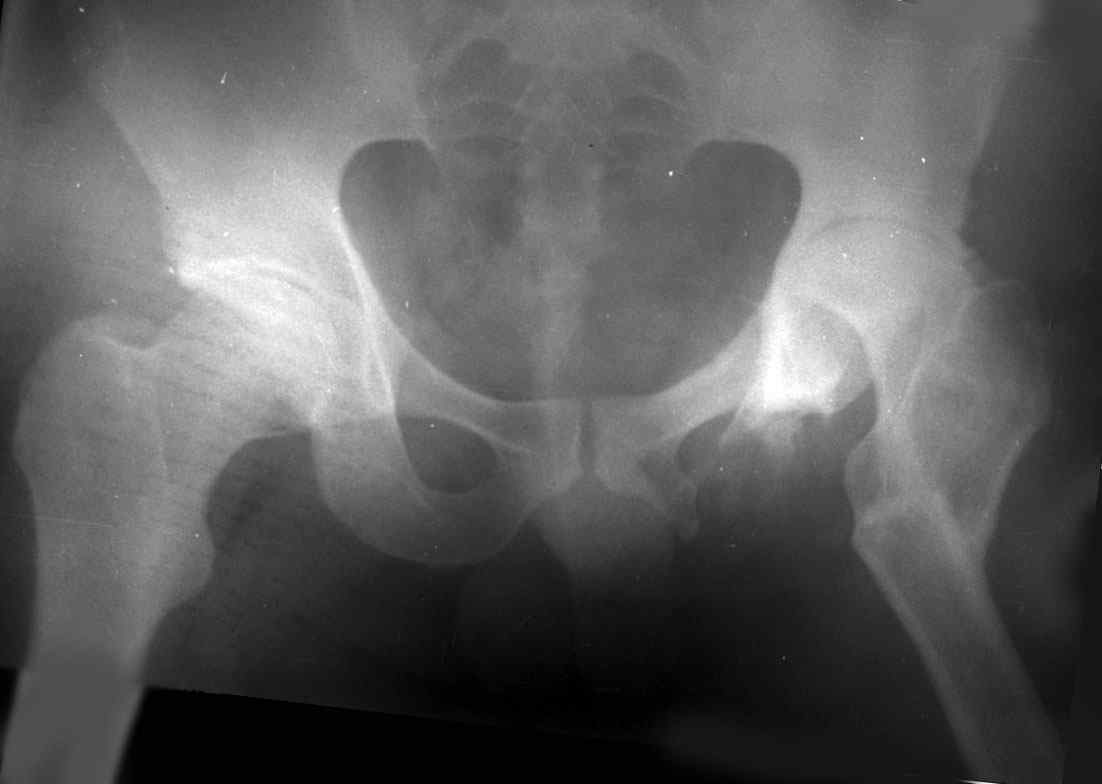

Поднят очень интересный вопрос об эффективности создания опорного бедра по Илизарову у молодых пациентов (ок). Наверное мне не повезло и я не

видел положительных результатов после этих операций, а вот проблемных больных приходится видеть достаточно часто. Причем сроки их обращения

после остеотомии короткие - 3-5 лет, а выполнение эндопротезирования после остеотомии на двух уровнях с многоплоскостной деформацией является

серьезным испытанием и для пациента и для хирурга. Я тоже не сторонник эндопротезирования в молодом возрасте, но уж после неудачных остеотомий

просто нет другого выхода. Проблема еще заключается в том, что каждый из нас видет ограниченное кол-во больных и в разные сроки. Детско-юношеские ортопеды наблюдают больных только до взрослого возраста, а дальше они

уходят из-под контроля. Современные эндопротезы дают хорошие и устойчивые результаты, поэтому не думаю, что ответ однозначный в пользу

остеотомии. Я представил Р-граммы больных с неудачными р-ми после остеотомий.

Эндопротезирование у них было на порядок сложнее в отличие от артропластики без проведения остеотомии.